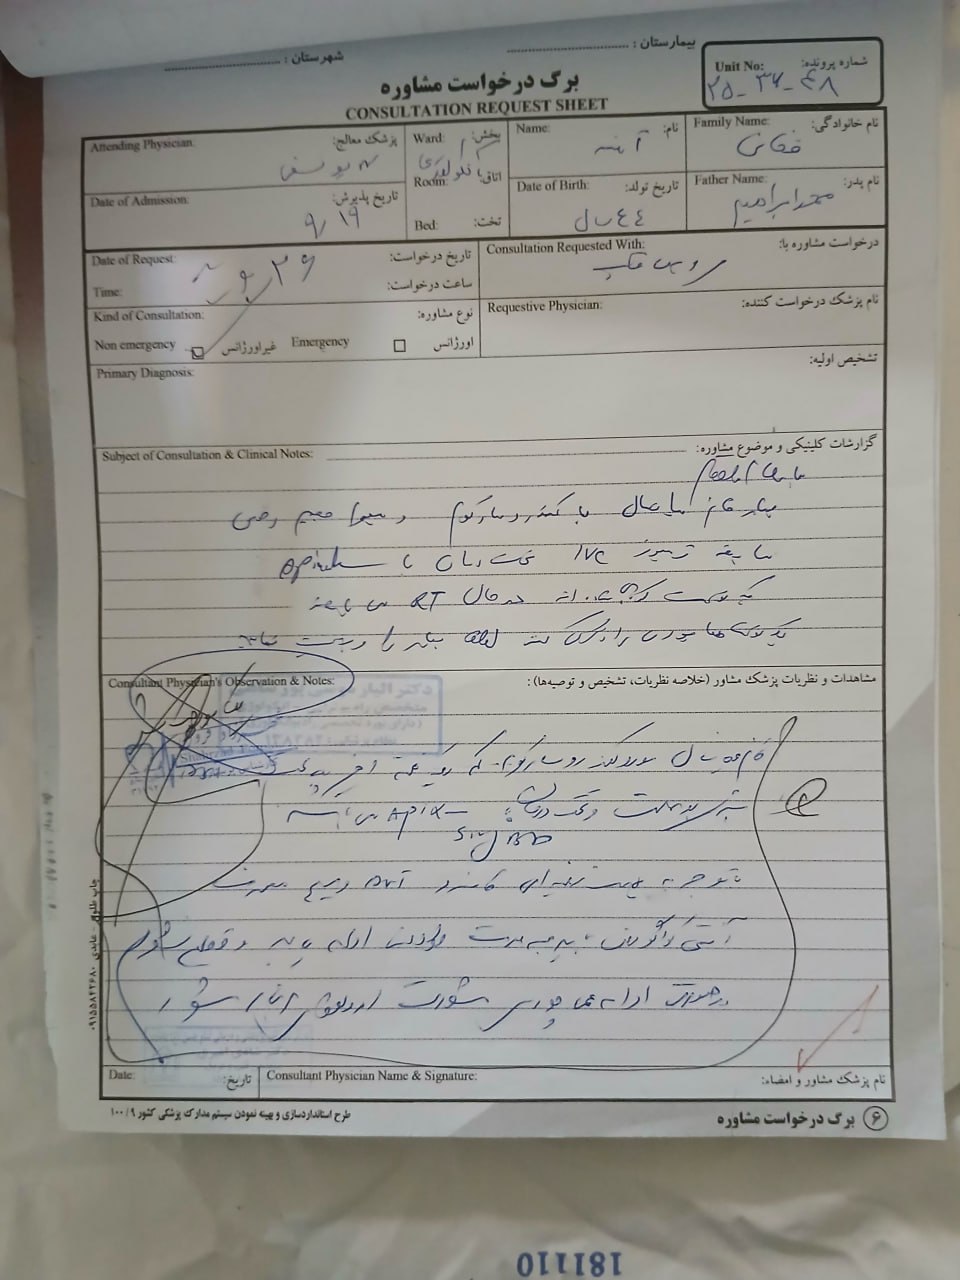

(تصویر مربوط به این مراجعه نیست) Other:

(تصویر مربوط به این مراجعه نیست) Other:

(تصویر مربوط به این مراجعه نیست) Other:

(تصویر مربوط به این مراجعه نیست) Other:

(تصویر مربوط به این مراجعه نیست) Other:

(تصویر مربوط به این مراجعه نیست) Other:

(تصویر مربوط به این مراجعه نیست) Other:

(تصویر مربوط به این مراجعه نیست) Other:

(تصویر مربوط به این مراجعه نیست) Other:

(تصویر مربوط به این مراجعه نیست) Other:

(تصویر مربوط به این مراجعه نیست) Other:

(تصویر مربوط به این مراجعه نیست) Other:

(تصویر مربوط به این مراجعه نیست) Other:

(تصویر مربوط به این مراجعه نیست) Other:

(تصویر مربوط به این مراجعه نیست) Other:

(تصویر مربوط به این مراجعه نیست) Other:

(تصویر مربوط به این مراجعه نیست) Other:

(تصویر مربوط به این مراجعه نیست) Other:

(تصویر مربوط به این مراجعه نیست) Other:

(تصویر مربوط به این مراجعه نیست) Other:

(تصویر مربوط به این مراجعه نیست) Other:

(تصویر مربوط به این مراجعه نیست) Other:

(تصویر مربوط به این مراجعه نیست) Other:

(تصویر مربوط به این مراجعه نیست) Other:

(تصویر مربوط به این مراجعه نیست) Other:

(تصویر مربوط به این مراجعه نیست) Other:

(تصویر مربوط به این مراجعه نیست) Other:

(تصویر مربوط به این مراجعه نیست) Other:

(تصویر مربوط به این مراجعه نیست) Other:

(تصویر مربوط به این مراجعه نیست) Other:

(تصویر مربوط به این مراجعه نیست) Other:

(تصویر مربوط به این مراجعه نیست) Other:

(تصویر مربوط به این مراجعه نیست) Other:

(تصویر مربوط به این مراجعه نیست) Other:

(تصویر مربوط به این مراجعه نیست) Other:

(تصویر مربوط به این مراجعه نیست) Other:

(تصویر مربوط به این مراجعه نیست) Other:

(تصویر مربوط به این مراجعه نیست) Other:

(تصویر مربوط به این مراجعه نیست) Other:

(تصویر مربوط به این مراجعه نیست) Other:

(تصویر مربوط به این مراجعه نیست) Other:

(تصویر مربوط به این مراجعه نیست) Other:

(تصویر مربوط به این مراجعه نیست) Other:

(تصویر مربوط به این مراجعه نیست) Other:

(تصویر مربوط به این مراجعه نیست) Other:

(تصویر مربوط به این مراجعه نیست) Other:

(تصویر مربوط به این مراجعه نیست) Other: